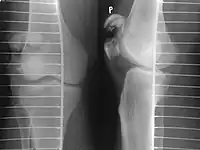

Transverse fracture of patella